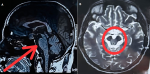

A patient in their 60s presented with a progressive history over two years of unsteadiness of gait, frequent falls, impaired coordination, and slurred speech. Neurological examination revealed axial rigidity, bradykinesia, intentional tremors of the upper limbs, wide-based ataxic gait, limb dysmetria, impaired rapid alternating movements, and increased tone with cogwheel rigidity. Vertical gaze palsy consistent with supranuclear ophthalmoplegia was noted. These clinical features are indicative of progressive supranuclear palsy (PSP) with cerebellar involvement. The magnetic resonance imaging findings revealed, in the sagittal T1-weighted sequence (A: red arrow), marked atrophy of the midbrain tegmentum with relative preservation of the pons, producing the classical "hummingbird sign" (also known as the "penguin sign"), an established neuro-imaging hallmark supportive of PSP diagnosis. Significant atrophy of the cerebellum, particularly affecting the vermis and hemispheres, contributes to the enlargement of the fourth ventricle. The axial T2-weighted sequence (B: red circle) at the midbrain level shows characteristic atrophy with reduction in the anteroposterior diameter of the midbrain tegmentum, consistent with the "Mickey Mouse sign", another well-recognised radiologic marker supportive of PSP. Cerebellar atrophy is evident as volume loss in the cerebellar hemispheres, visible on these axial slices. Together, these clinical and imaging findings confirm the diagnosis of the cerebellar phenotype of PSP (PSP-C). Recognition of this variant is essential for guiding management, which primarily involves supportive care through physiotherapy and occupational therapy, as pharmacological treatment responses are typically limited. Early diagnosis facilitates fall prevention strategies, tailored rehabilitation, and patient and caregiver counselling regarding disease progression.

Figure 1: A,B) sagittal T1-weighted (red arrow points) and axial T2-weighted (red circle highlights)